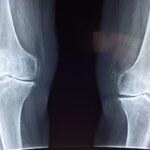

Knee pain:

knee pain Its causes can be divided according to the patient’s age. In young people, the cause is usually injury to one of the ligaments in the knee joint, such as the cruciate ligament or meniscus. In contrast, in the elderly, the cause is usually cartilage on the surface of the joint, which erodes and leads to increased friction of the knee joint.

Knee Osteoarthritis

Count Knee roughness It is one of the most common joint diseases, and occurs as a result of erosion of smooth cartilage which covers the surfaces of the joint, resulting in Bone friction together Symptoms such as pain, stiffness, and difficulty moving appear.

The possibility of contracting it increases with Aging, weight gain, or repetitive physical exertionIn addition to genetic factors and old joint injuries.

Degrees of knee Osteoarthritis and treatment of each degree

First degree: the beginning of osteoarthritis

At this stage the cartilage is still relatively intact, with a slight onset of wear seen on x-rays. The patient feels mild pain after walking or exerting effort.

Treatment:

Grade II: Mild To moderate Knee arthritis

The pain begins to increase, especially when climbing stairs or standing for long periods, and slight narrowing of the joint appears on x-rays.

Grade III: Advanced Knee OA

Symptoms clearly increase with difficulty bending the knee, and the x-rays show severe erosion of the cartilage and the surfaces of the bones getting closer together.

Grade 4: Extreme Knee Osteoarthritis

At this stage the cartilage is almost completely eroded, resulting in direct friction between the bones and deformation of the joint shape with constant pain even at rest.

- Surgical intervention to change the entire knee joint (Total Knee Replacement).

- Post-operative rehabilitation to restore normal movement and improve quality of life.

Early diagnosis and treatment

Helps Early diagnosis of knee osteoarthritis To control symptoms and avoid the development of the condition. This is done through careful clinical examination and x-rays, with an appropriate treatment plan developed according to the degree of roughness.